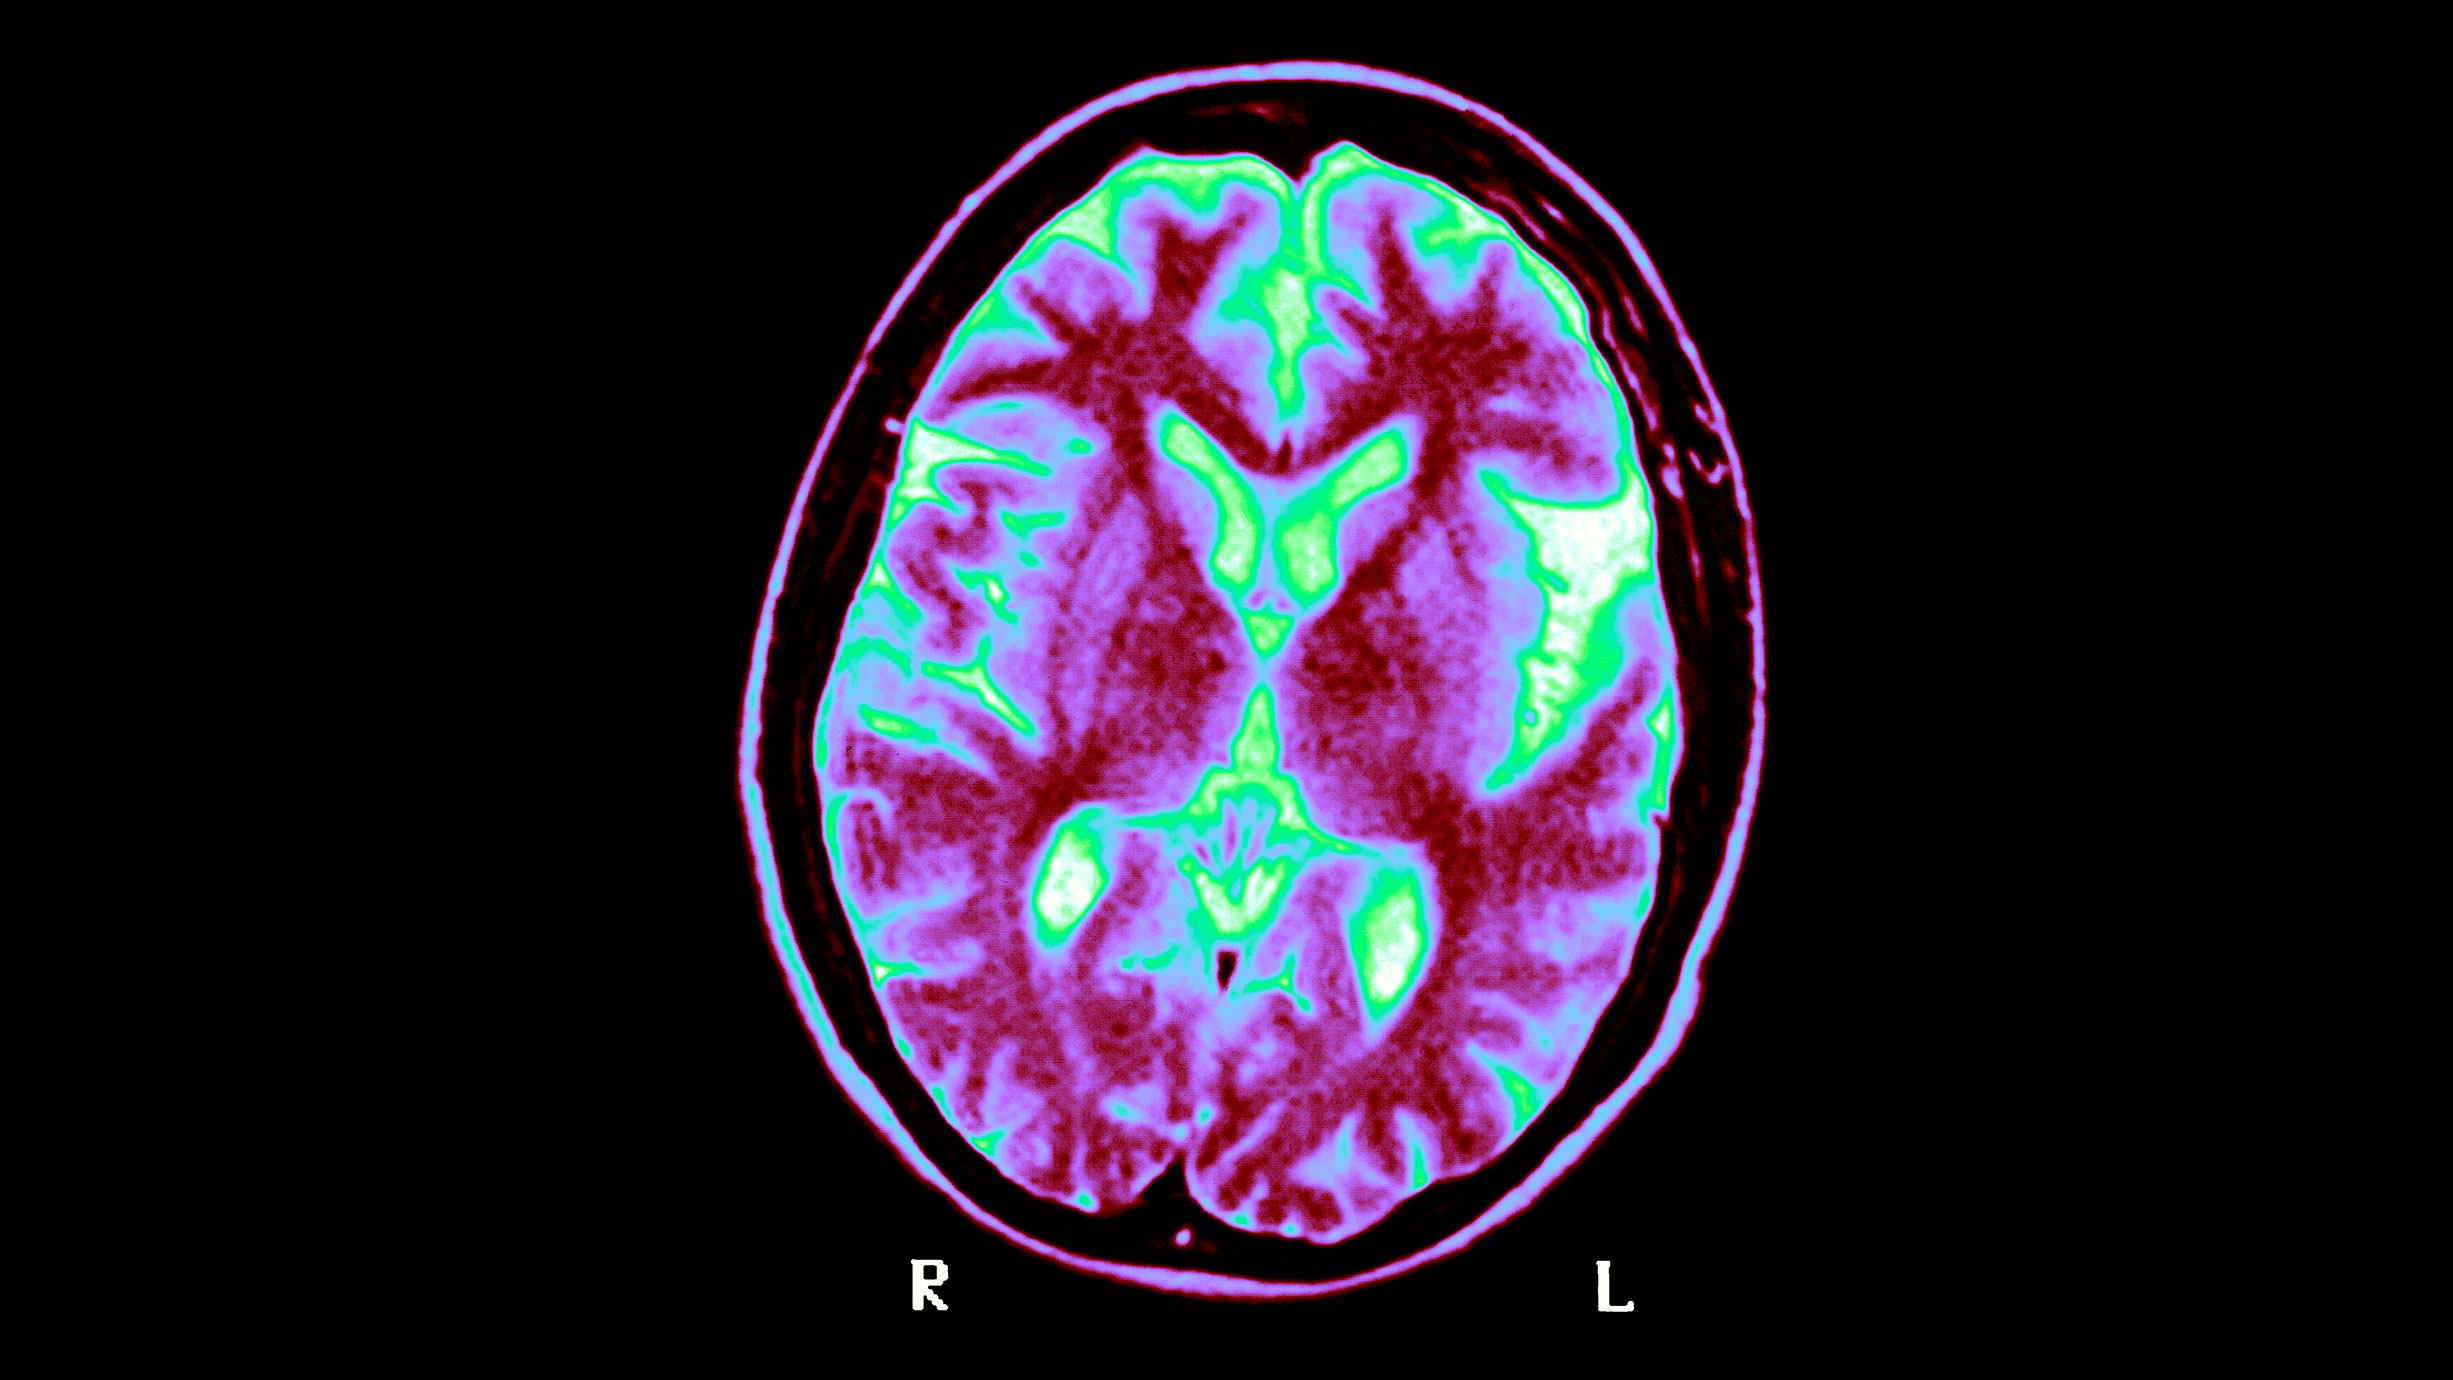

Billede fra hjernescanning. Foto: BSIP/Getty Images

Hjernescanninger er et almindeligt redskab til at undersøge, om en person har udviklet alzheimer. Billedet er ikke fra den igangværende forskning. Foto: BSIP/Getty Images

I både det korte og det længere forsøg kunne lægerne ved afslutningen spore en forbedring i de kognitive funktioner – altså evnen til at udføre nogle tests, der indikerer hjerneproblemer – blandt patienter, der brugte den nyudviklede lysteknologi. Hjernescanninger viste desuden, at hos dem, der i det længere forsøg fik den aktive behandling, var der tegn på forbedringer i selve hjernen.